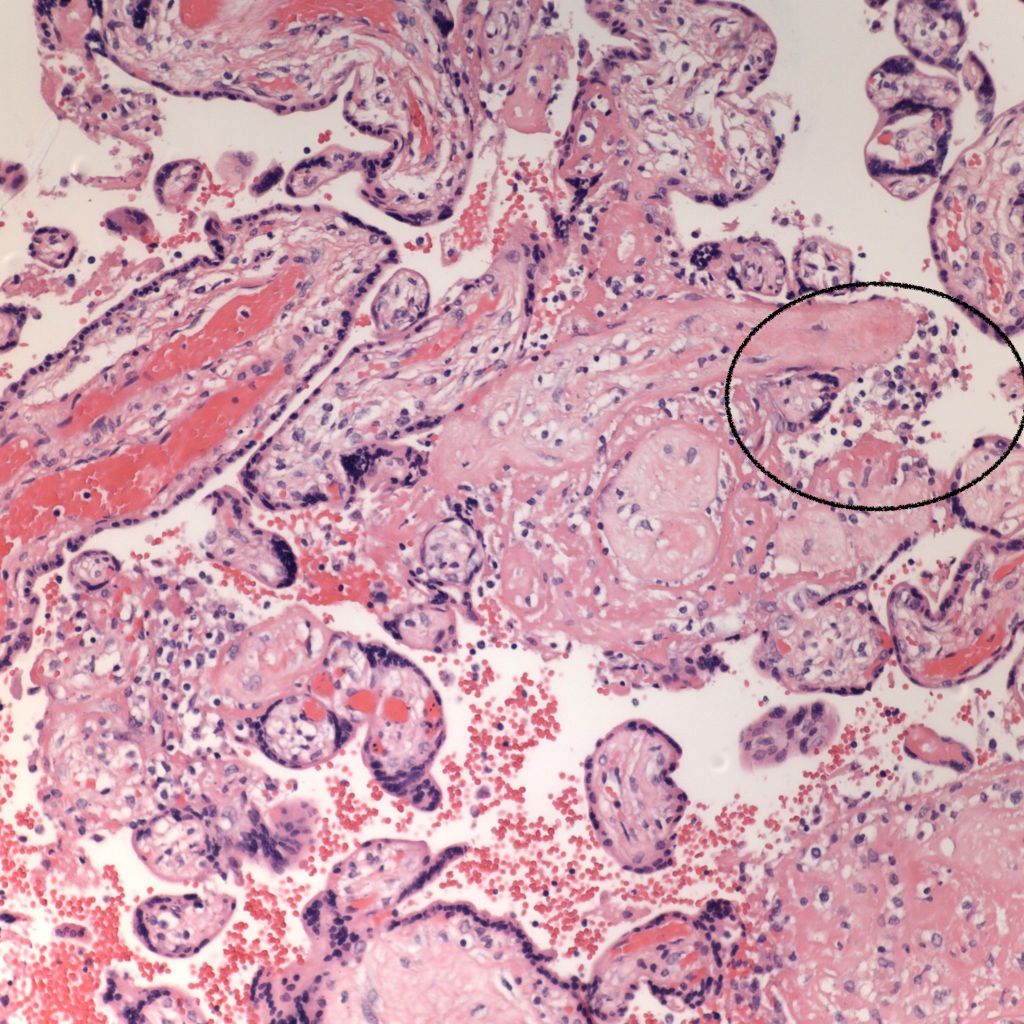

CHIV associated with Villitis of Uknown Etiology (VUE)

This pattern could be due to a primary cause of VUE with incidental chemotaxis of monocytes, two pathogenetically interrelated processes, or an incidental focus of VUE in a predominant CIIV disease. Currently, describing the extent of each process and its colocalization or lack of may prove useful until a better way to classify the co-existing lesions can be developed. One study has shown that there is a dichotomy between cases with c4d staining and those without c4d staining18.